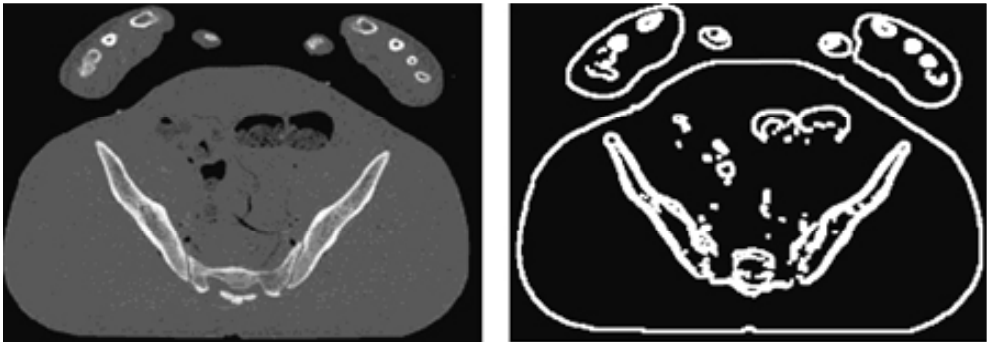

- 그 후 Canny edge detector를 사용하여 edge를 추출한다. (아래 그림 참고) Canny edge detector는 스케일 위치를 계산할 때 적합한 시작점이다.

- 각 세그먼트에 대해 연관된 포인트들을 살펴본다. 매칭이 수행되어 가장 일치하는 항목들을 얻는다. 매치 포인트는 SSD를 사용하여 얻는다. 특정 픽셀에서 SSD 값이 작을수록 해당 픽셀 근처의 첫번째 이미지와 두번째 이미지 사이에 더 많은 유사성이 존재한다.